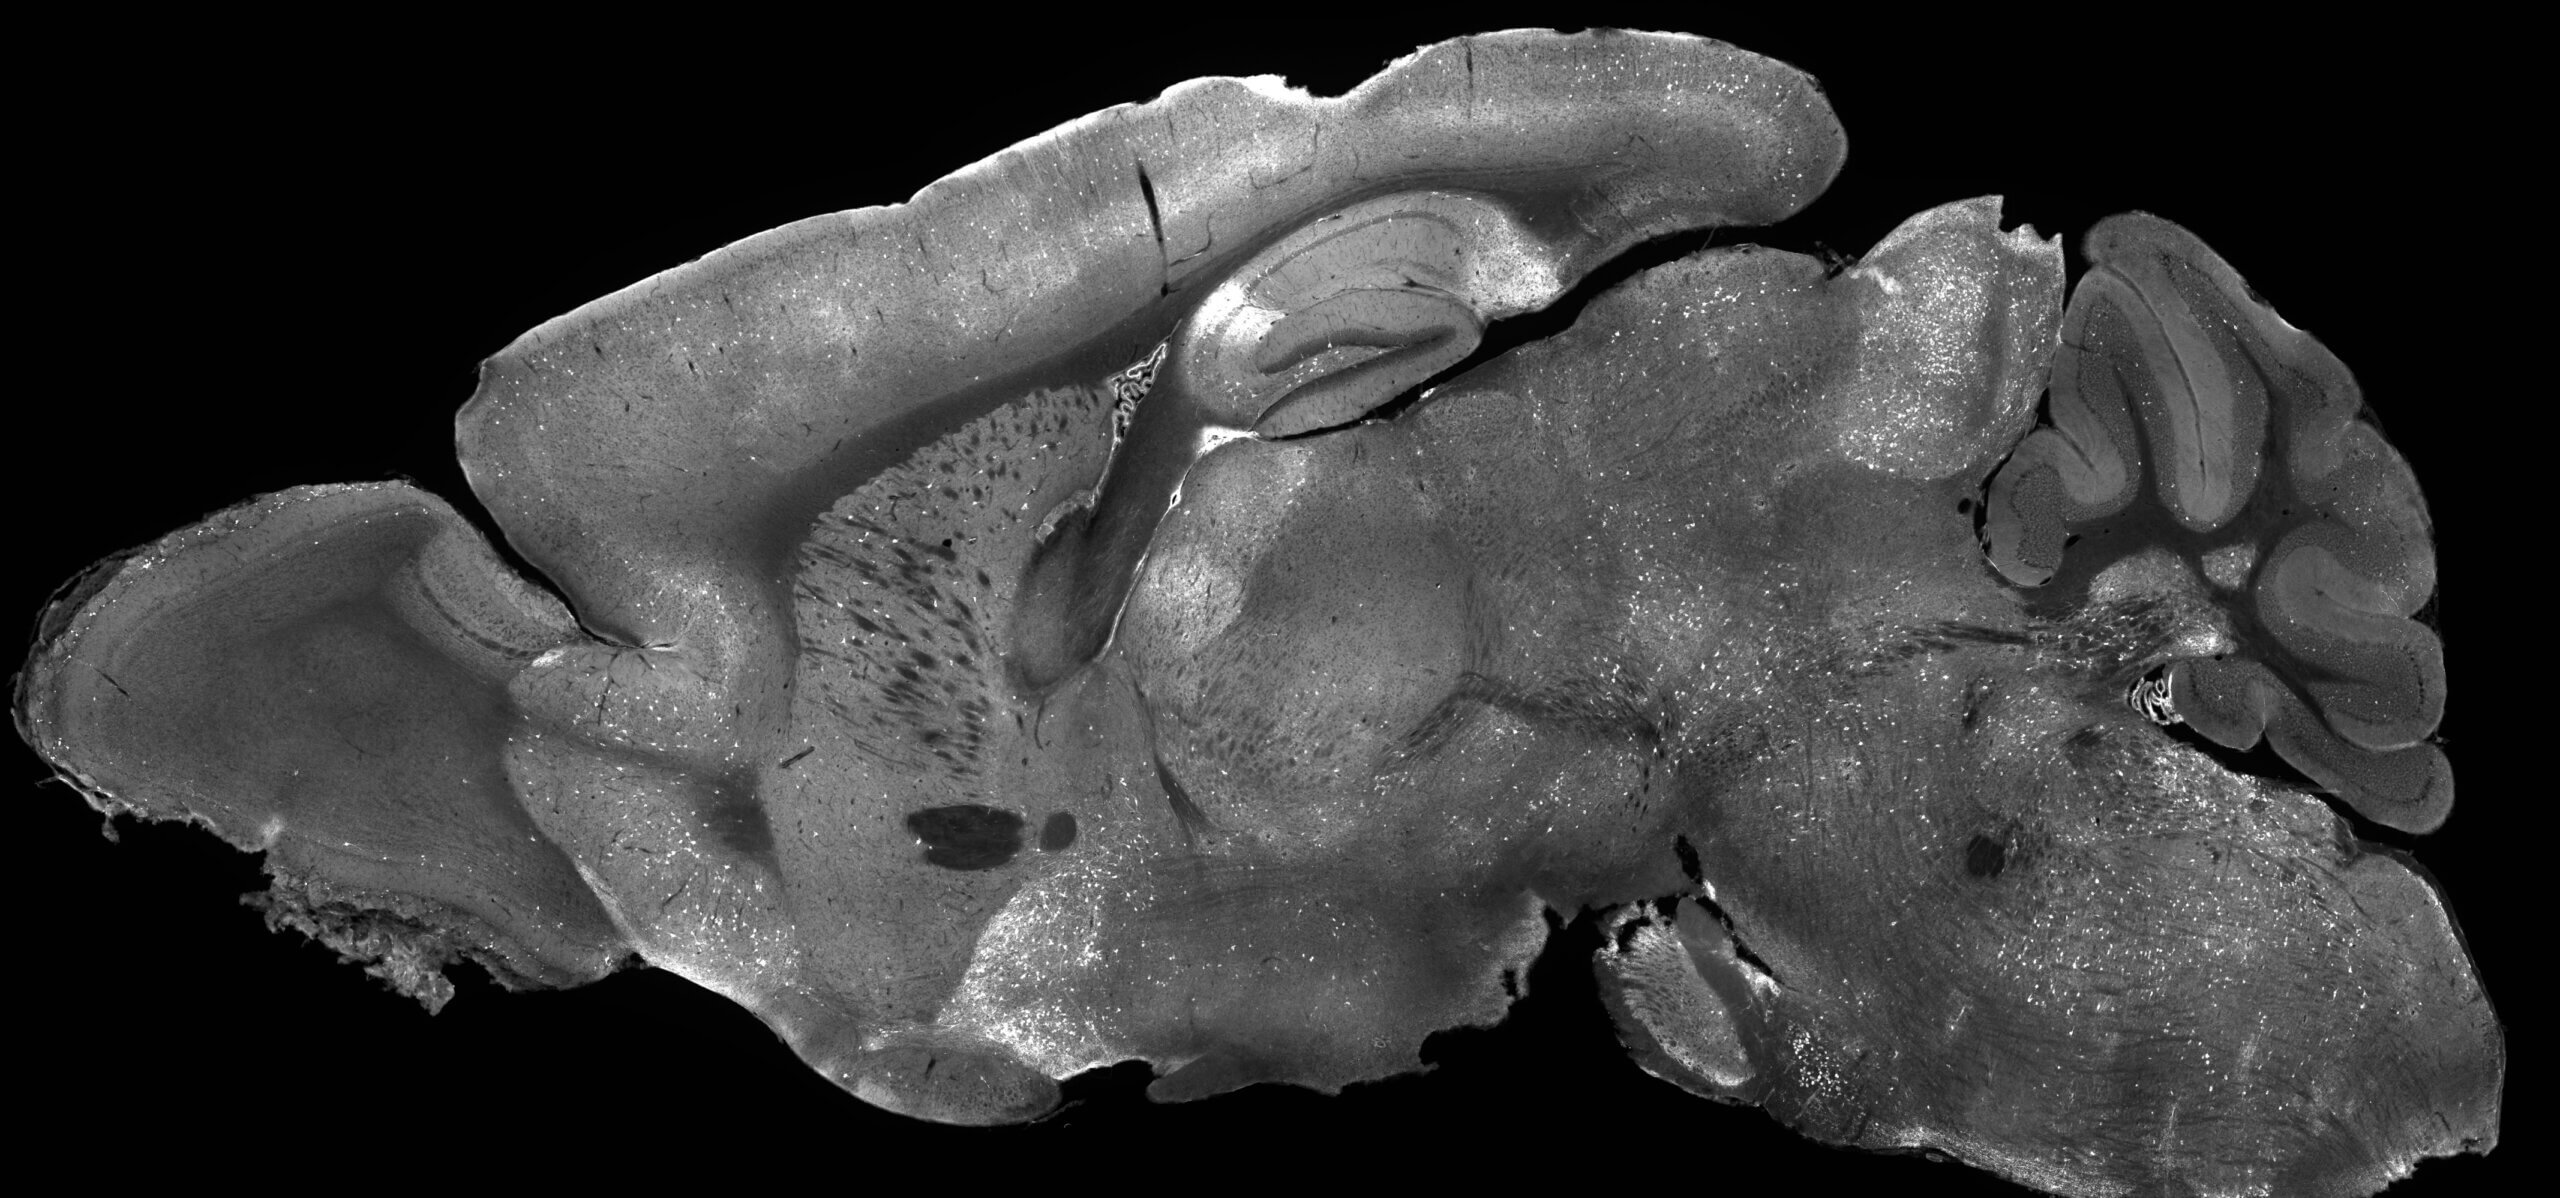

The findings, recently published in the journal Molecular Therapy, represent the first successful gene supplementation therapy for SRDs in which an adeno associate virus (AAV) was used to deliver a working copy of the SYNGAP1 gene into brain cells. AAVs are non-replicating viruses that act like delivery trucks carrying therapeutic cargo, in this case the SYNGAP1 gene, into cells that need it.

The new gene therapy improved a broad range of disease symptoms, nearly eliminating epileptic brain activity and correcting hyperactive behavior and risk-taking tendencies characterized by SRDs. The treatment also substantially restored normal brain wave patterns, which is significant because abnormal brain rhythms in SRD patients are tied to cognitive dysfunction affecting learning, memory, and attention.

Scientists faced a technical barrier in designing the new therapy. The defective copy of the SYNGAP1 gene needs to be replaced, but this gene is too large to fit into AAV delivery systems. In this case, researchers built the oversized gene and packaged it into the AAV, much like loading a truck filled with more luggage than anyone thought it could hold. Surprisingly, it all fit, and the therapy was successfully delivered into targeted brain cells.